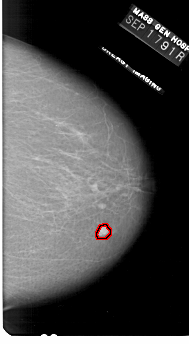

A_1727_1.LEFT_MLO

RIGHT_MLO LINES 6511 PIXELS_PER_LINE 3451 BITS_PER_PIXEL 12 RESOLUTION 43.5 OVERLAY

FILE: A_1727_1.RIGHT_MLO.OVERLAY

TOTAL_ABNORMALITIES 1

ABNORMALITY 1

LESION_TYPE MASS SHAPE LOBULATED MARGINS CIRCUMSCRIBED

ASSESSMENT 5

SUBTLETY 5

PATHOLOGY MALIGNANT

TOTAL_OUTLINES 1

BOUNDARY